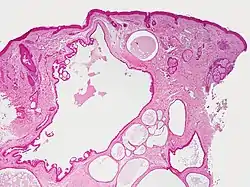

Hidrocystoma, also known as cystadenoma,[1] is a small bump, a cyst of a sweat duct, usually on the eyelids.[2] It may be flesh-coloured, have a bluish tint in white skin or be darker in black skin.[3]

There are three types of "sweat" glands: True sweat glands or eccrine glands; sebaceous glands, which have an oily secretion around hair follicles; and apocrine glands which have more oily product than eccrine glands and are found on the face, armpit, and groin.

Hidrocystomas usually arise from apocrine glands. There may be a type of hidroadenoma that arises from eccrine glands, but these are uncommon.